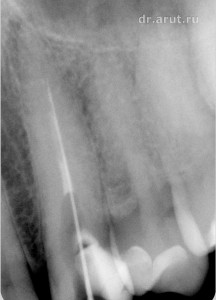

Пациен С. обратился в стоматологическую клинику с жалобой на боль в 23 зубе, усиливающуюся при накусывании. Изучение анамнеза заболевания, благодаря наличию истории болезни пациента с записями за последние 5 лет, установило, что в 2010 году 23 зуб был лечён по поводу обострения хронического периодонтита.

- Хронический периодонтит (Rg-графия 2010-го года)

5 лет назад, на момент обострения хронического периодонтита, канал уже был запломбирован, и врач-стоматолог попытался его распломбировать. Но к сожалению попытка не увенчалась успехом. В итоге канал был запломбирован на 2/3-3/4 длины (проходимая часть) форфенаном и гуттаперчиевыми штифтами. После лечения наступила 5-летняя ремиссии, закончившаяся в настоящее время и приведшая к очередному обострению хронического периодонтита.

Объективно: Зуб изменён в цвете. На окклюзионно-дистальной поверхности пломба, занимающая более 80% поверхности. Перкуссия болезненная, ЭОД выше 100µА. Во время ренгенологического исследования в области верхушки корня 23 зуба обнаружен участок просветления с нечёткими контурами размером 3-4 мм.